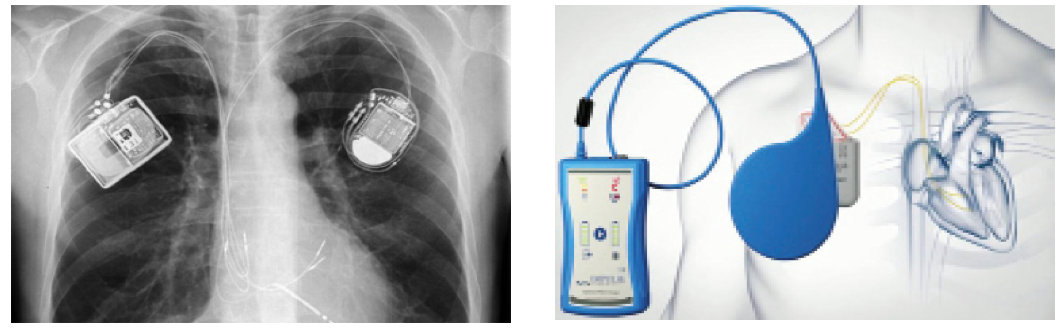

Таким образом, при наличии показаний для установки ИКД в настоящий момент рекомендуется добавлять СРТ для улучшения симптоматики, повышения толерантности к физической нагрузке, уменьшения количества госпитализаций у пациентов, страдающих ХСН, на оптимальной медикаментозной терапии с ФВ ЛЖ <35% и полной блокадой левой ножки пучка Гиса (рис. 1).

Рис. 1. Рентгенограмма пациента с имплантированным СРТ